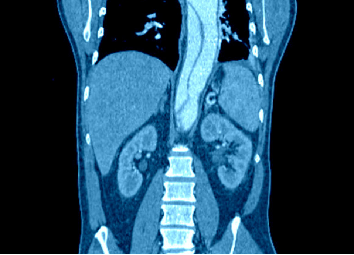

以上是他的胸部CT影像,主要表现为左下肺炎症,片絮影+磨玻璃影。

腹部CT可见肠系膜及腹膜后淋巴结显著增大(直径常>2cm),病理特征为泡沫状巨噬细胞浸润,PAS染色阳性,此表现对鉴别诊断具有重要价值。

CT表现为双肺多发实性结节(直径0.5-3cm),结节边缘可见毛刺征及分叶征,特征性表现为短期内体积呈几何级数增长(如1周内增大10倍),需与转移瘤、结核球等鉴别。

混合性密度影与胸腔积液

40%病例出现磨玻璃影与实变影共存,部分结节中央可见液化坏死;30%伴单侧渗出性胸腔积液,积液分析呈渗出性但培养阴性,此表现易误诊为脓胸。